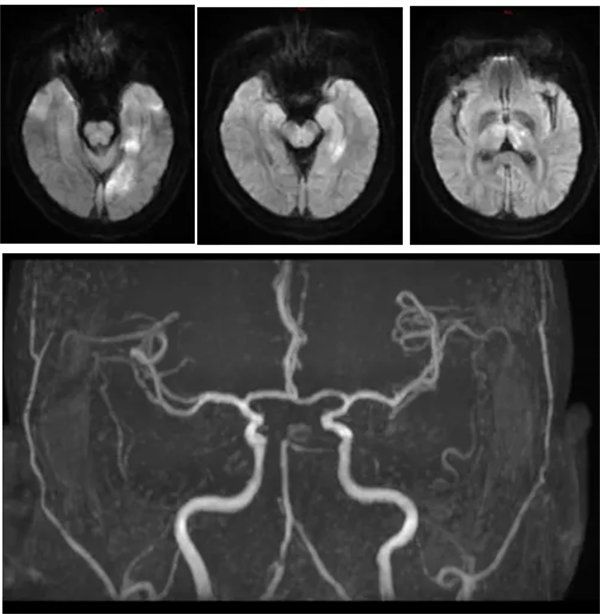

近日,42岁的张先生因突发头晕、右手无力、视物模糊10小时,意识不清10分钟,被家属发现后紧急送至我院急诊科,考虑脑卒中收入神经内三科进一步治疗,到达科室后患者已神志不清,且伴有呼吸浅快,大小便不能自控。NIHSS评分35分,mrs评分4分;行头颅DWI提示左侧颞枕叶、左侧丘脑急性脑梗死;颅脑MRA提示右侧大脑后及小脑上动脉未见显影,左侧大脑后动脉P1段明显变细,远端闭塞。